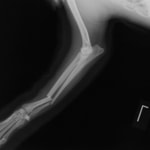

症例3:キルシュナーワイヤーのピンニングによる整復

ペルシャ猫 11ヶ月齢 雄

他院にて左大腿骨遠位の成長板骨折(salter-harrisⅠ型)が認められており、治療相談を目的として来院。当院にて、キルシュナーワイヤーを用いたピンニングにより骨折部位の整復を行いました。術後の経過は良好で、現在も経過観察中です。

術後レントゲン